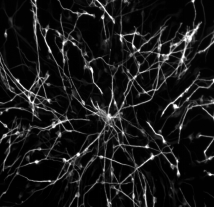

2、神经科学:用于监测神经元活动和大脑功能。